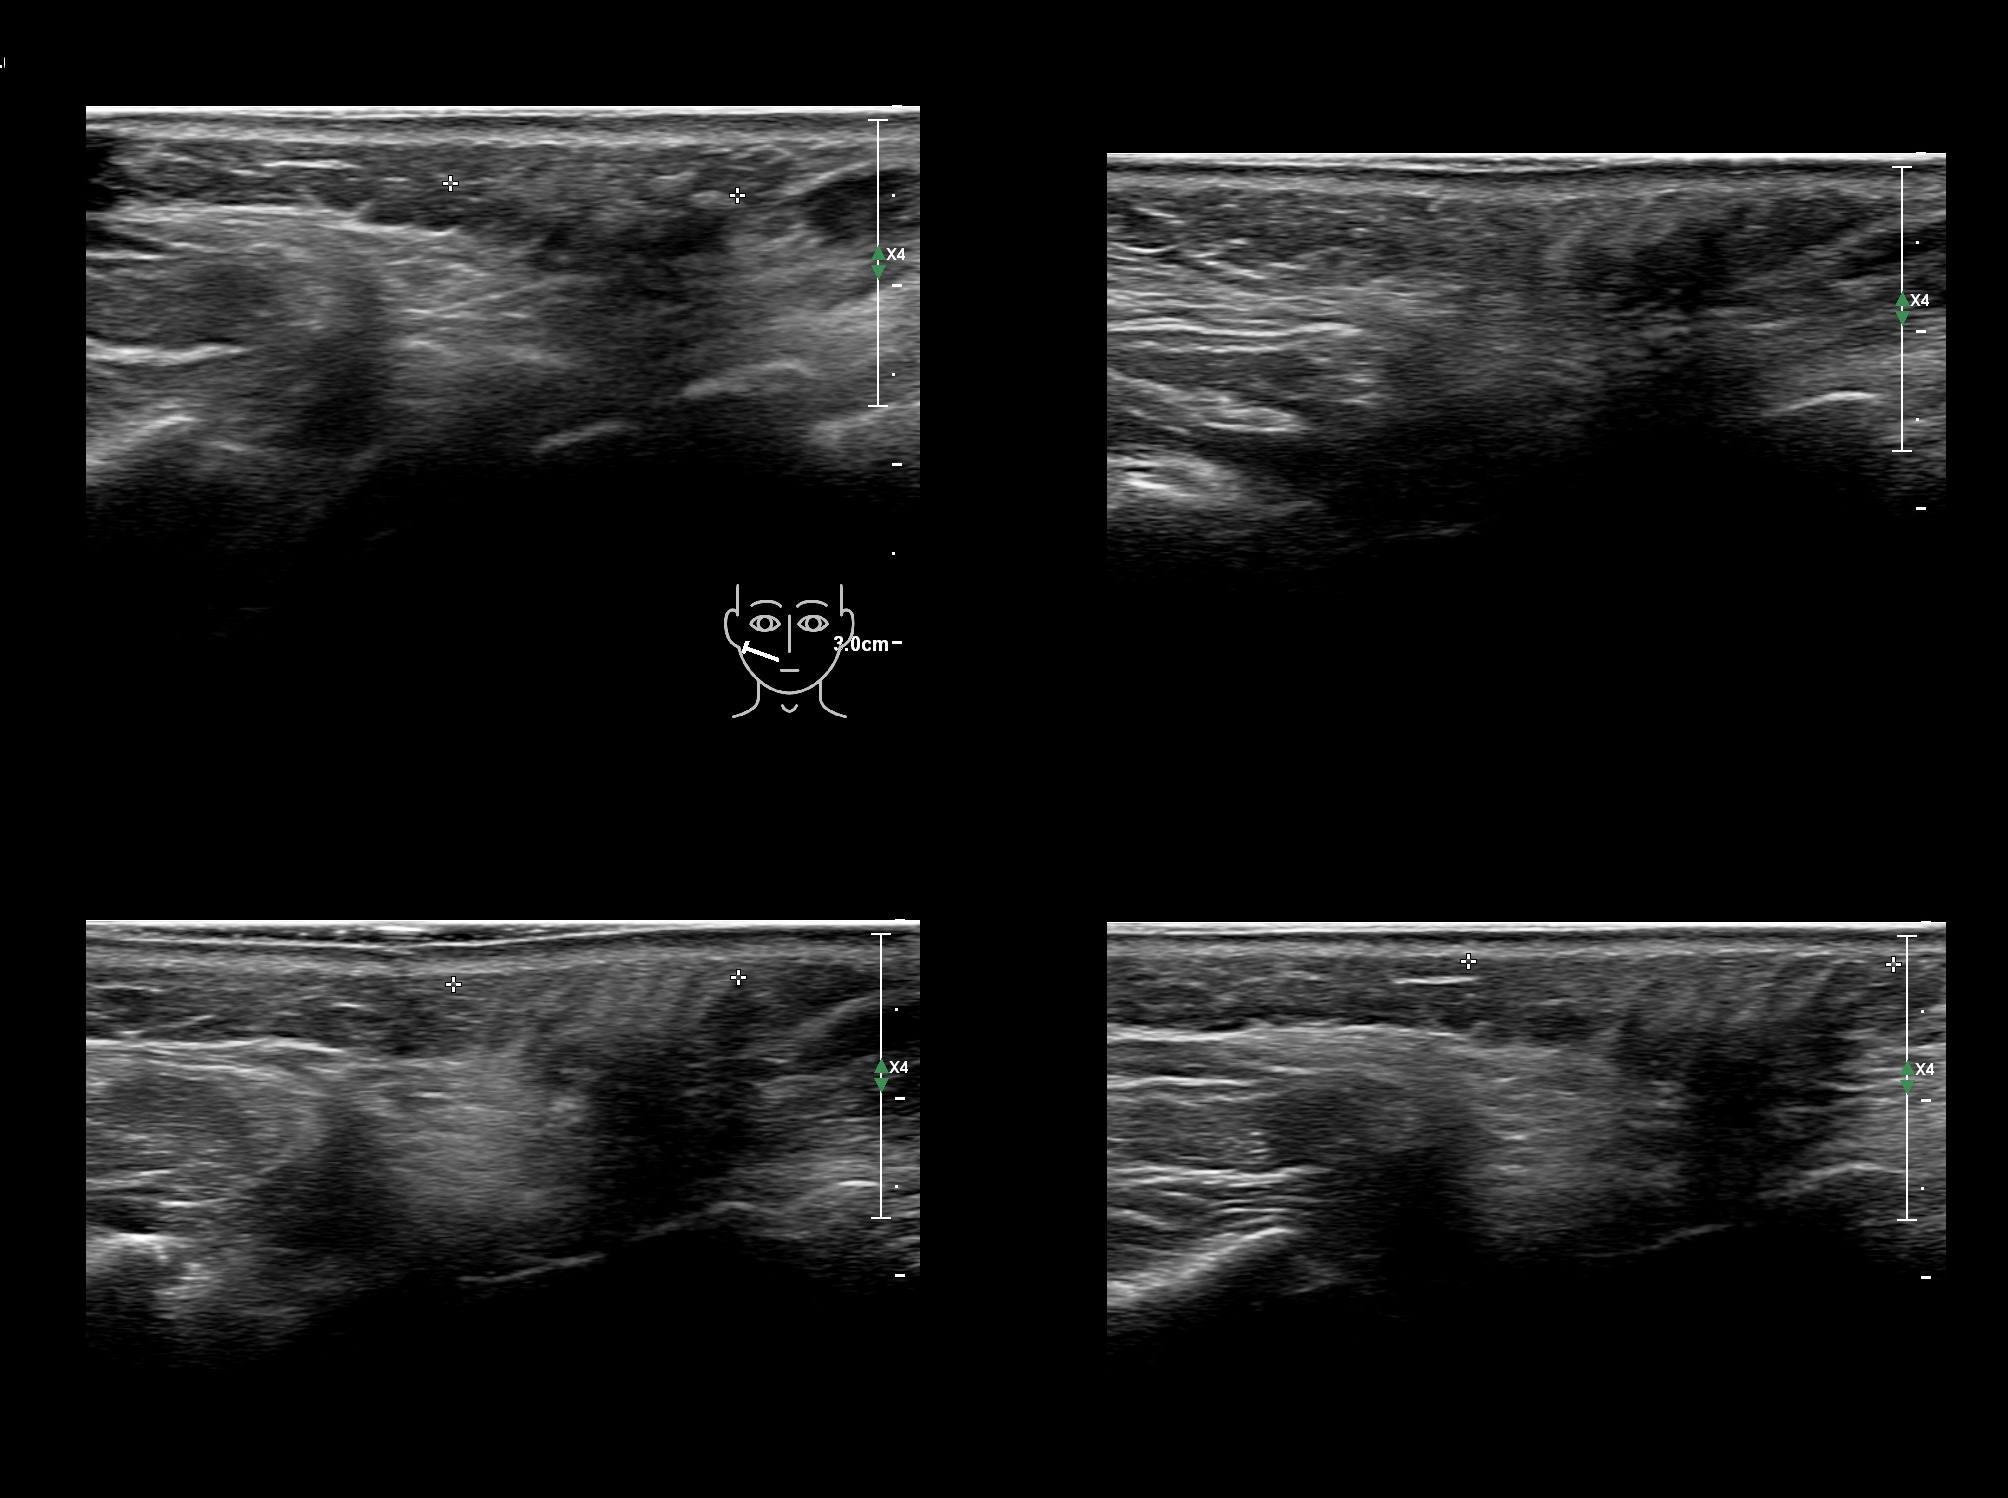

Draw in the second image below where the fillers are located. To check if your answer is correct, swipe the first image to the right.